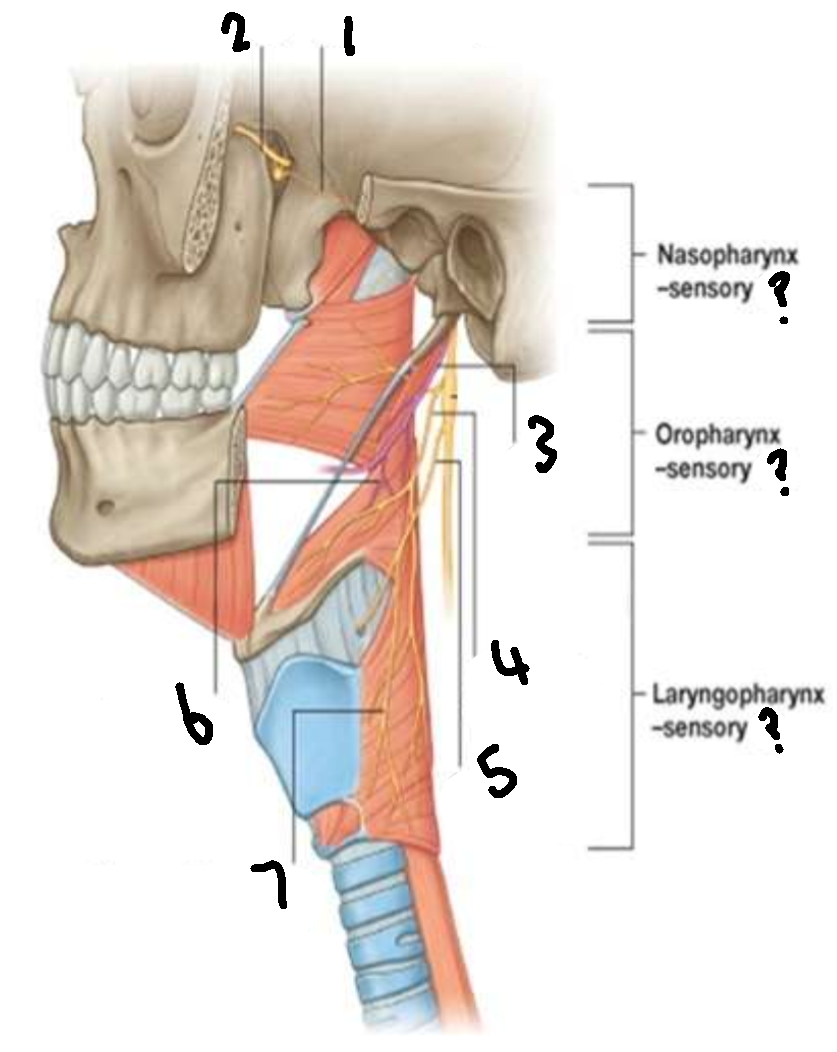

What provides sensory innervation to the nasopharynx?

mandibular branch of trigeminal V2

What provides sensory innervation to the oropharynx?

glossopharyngeal IX

What provides sensory innervation to the laryngopharynx?

vagus X

What is 1?

pharyngeal branch of V2

What is 2?

maxillary branch of trigeminal V2

What is 3?

glossopharyngeal IX

What is 4?

pharyngeal branch of vagus X

What is 5?

superior laryngeal nerve

What is 6?

pharyngeal branch of IX

What is 7?

external laryngeal branch of superior laryngeal nerve of X